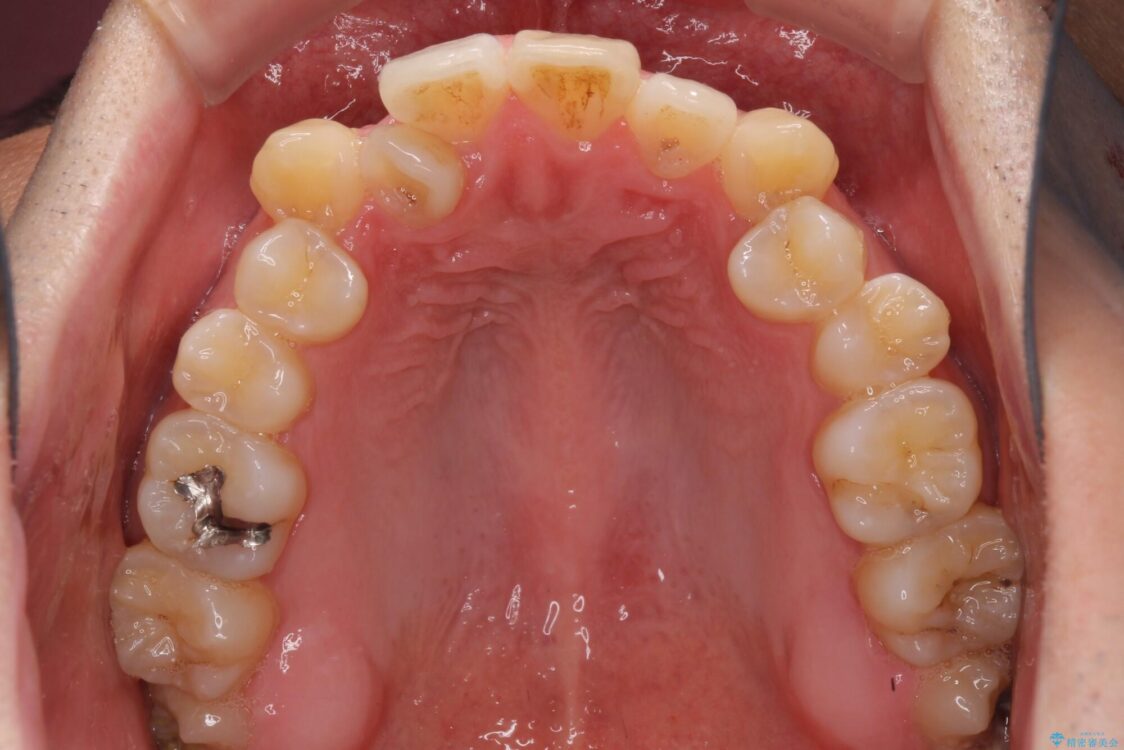

八重歯と前歯のデコボコを気にして来院された患者様です。

治療前

• 左右の八重歯が気になる ワイヤー装置での咬み合わせ改善 治療前画像